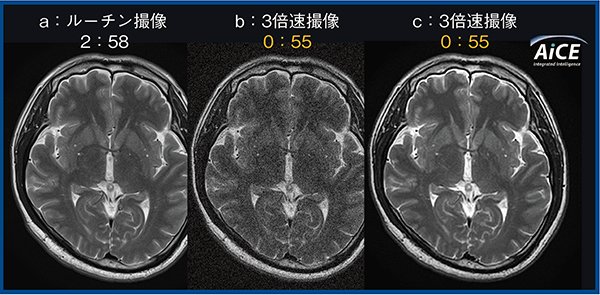

MRIにおいては,撮像時間,分解能,SNRの三者はそれぞれトレードオフの関係にある。したがって,ノイズ除去によるSNRの向上は,撮像時間を変えない高分解能化や画質(分解能とSNR)を保持した撮像時間短縮を可能とする。そこで,ボランティア10名の頭部T2強調画像を対象に,AiCE適用による撮像時間短縮に伴う画質劣化の有無について検証した。分解能を維持しつつ加算回数を減らし,parallel imagingでの加速ファクタ(acceleration factor)を増やす手法で,3倍速に短時間化を図った。

その結果,AiCEを適用した3倍速撮像は,ルーチン撮像とほぼ同等の画質になることが示された(図1)。また,神経放射線科医2名による定性評価でも,AiCE付加3倍速撮像はルーチン撮像とほぼ同等の画質という評価が得られた。一般的にノイズ除去法は病変のコントラストの悪化が懸念されるが,AiCEによるノイズ除去では診断に影響を与えた事象は認められていない。

図1 ルーチン撮像と3倍速撮像,AiCE付加3倍速撮像の比較